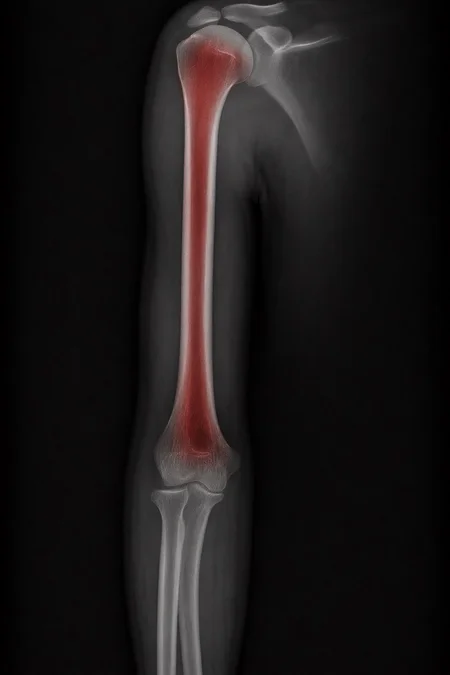

Can a model like Flux Kontext, designed for editing art and photography, be used to work with medical images, for example, with something 'as simple' as red-marking fractures?

The quick answer: it does do something interesting, but it over-scores and is far from reliable as a medical tool. It's a prototype to play with the idea, nothing more.

Test results:

False positives ≈ 24%

Fracture detection ≈ 20%

Sensitive mode (more detection, lots of noise)

Euler, 15 steps, Karras

Denoise 1.0

Result:

False positives ≈ 80%

Fracture detection ≈ 86%

Even more aggressive settings (e.g. rk beta57 to denoise 1.0) reach the absurd: 100% false positives and 100% detection: it paints everything red and almost hits all fractures beyond marking healthy areas, for an untrained eye.